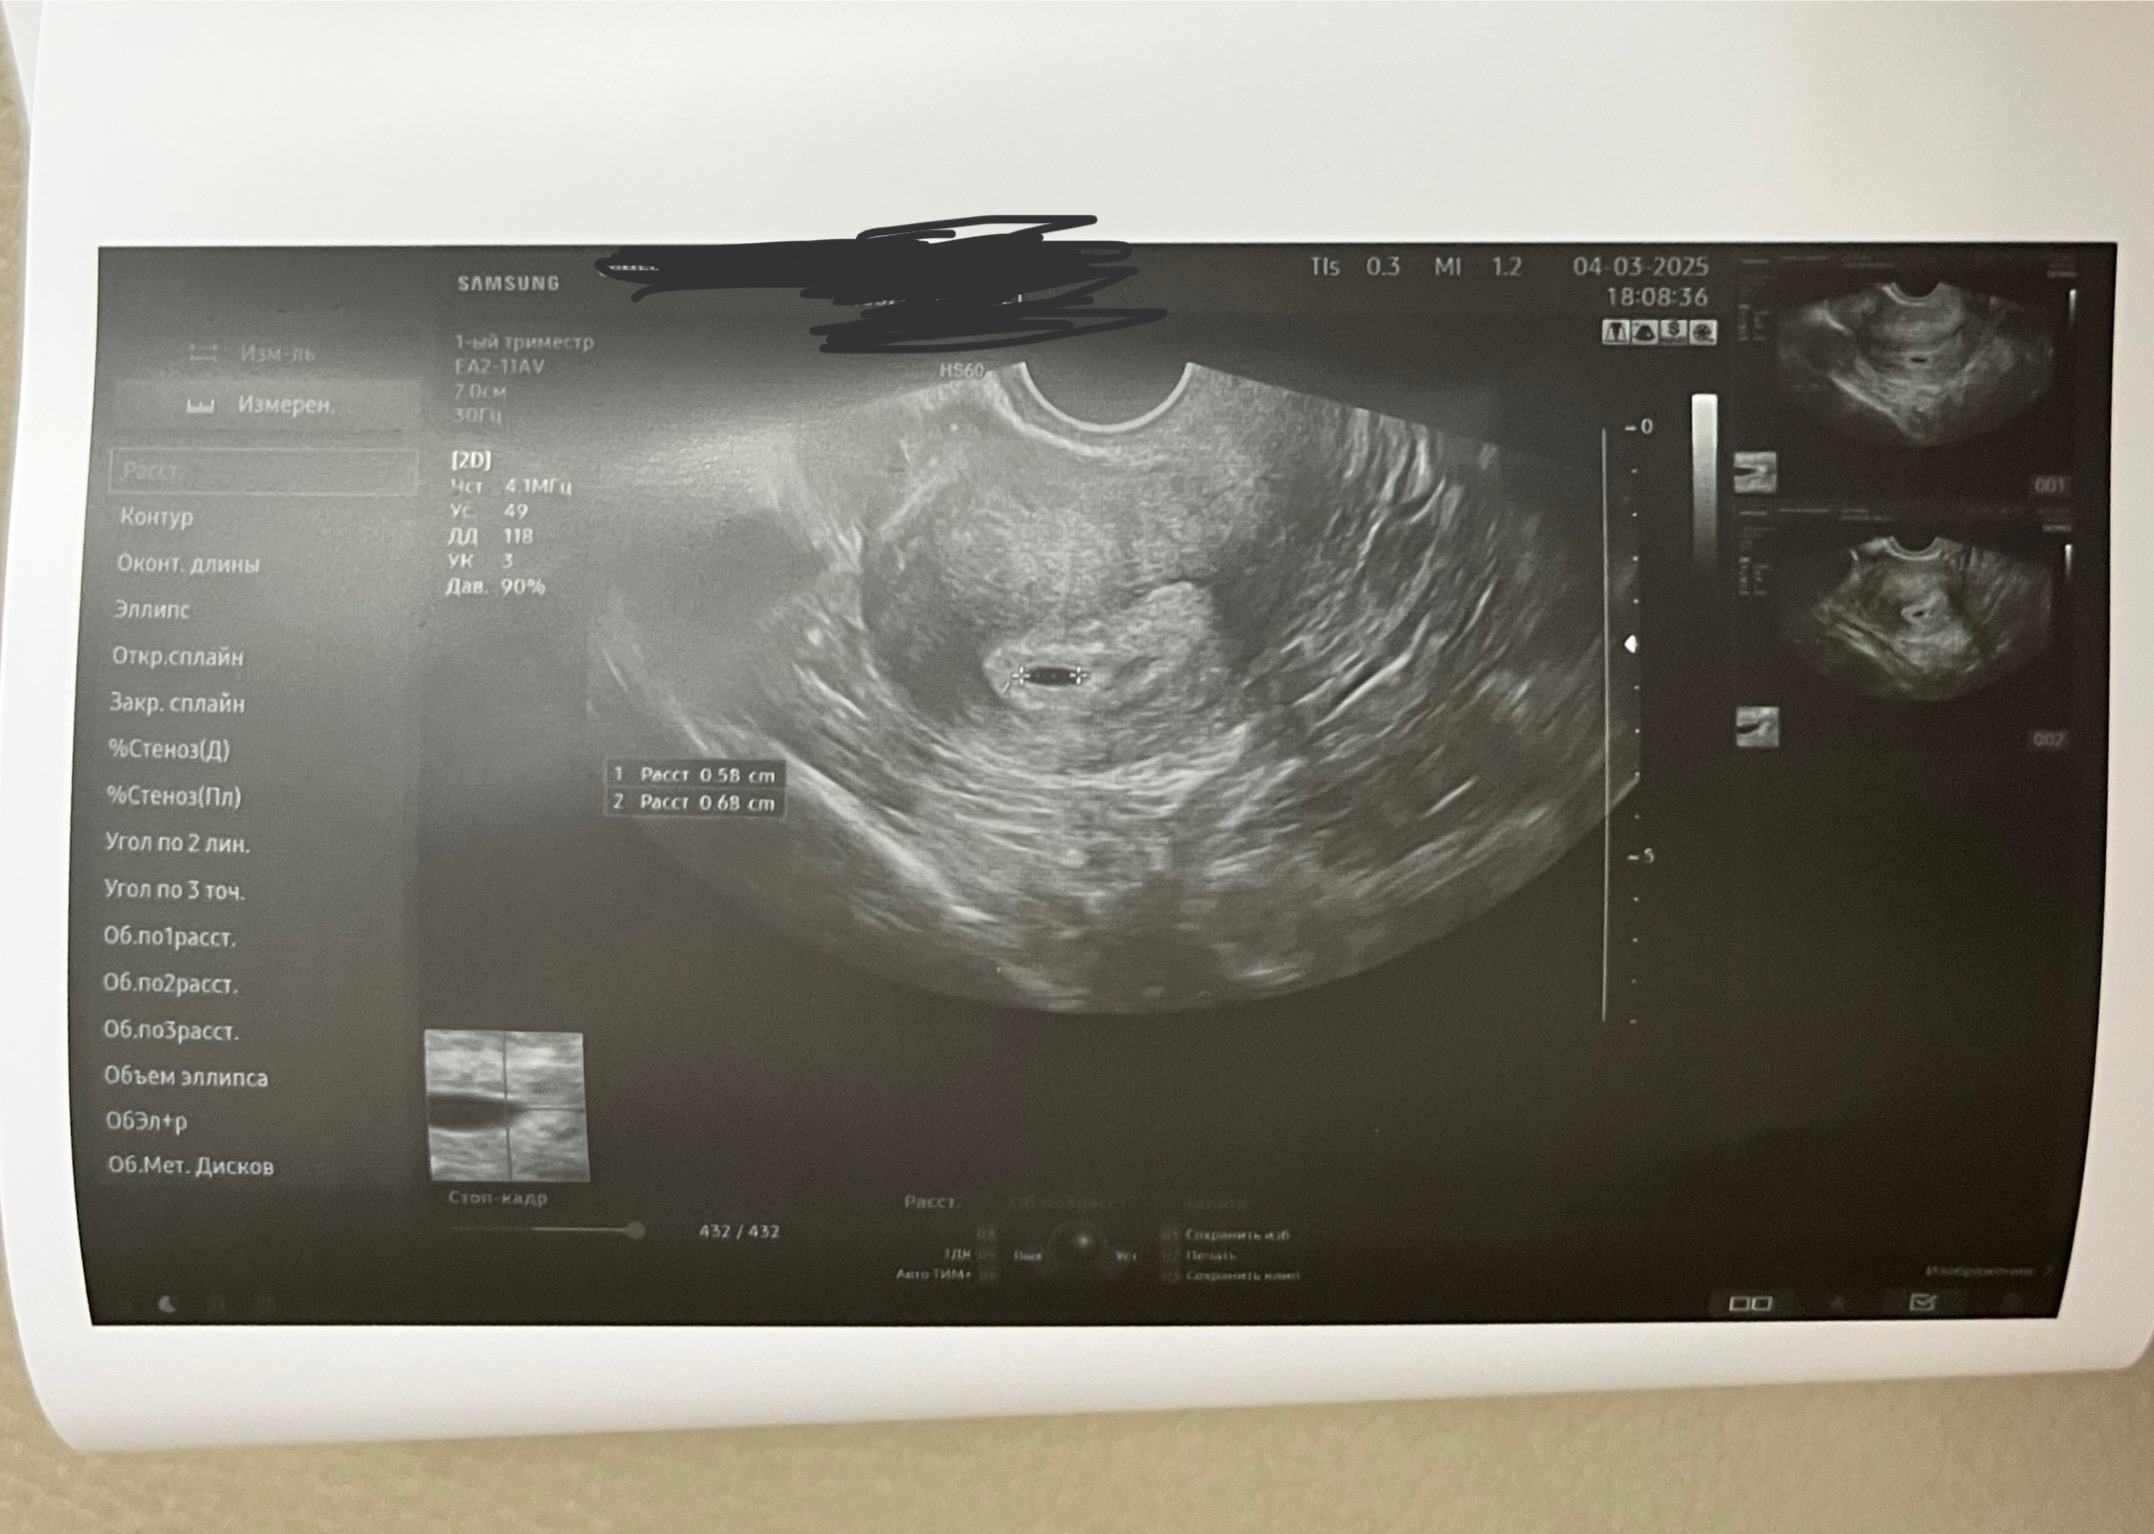

Беременность и угроза на раннем сроке

Не вижу проблем кроме тонус. Папаверин свечки и всё проедет. Переделать узи через неделю будет уже желт. меш. От плодного 8-10мм

Размер ПЯ вполне нормальный) у меня в 4 недели и 5 дней размер плодного яйца был 4мм) Тонус не так страшен, он может даже быть просто в момент узи (от переживаний, например). У меня тоже тонус был, плодное яйцо было вытянутое, магний сказали пить)

И еще я немного не понимаю, по размеру у меня 5 неделя, по дате зачатия тоже, но в заключении срок 1,5-2 недели, это как?

Нерпа, ну в принципе одно к другому соответствует, почему тогда мне сказали, что оно маленькое… Непонятно

У меня при первом узи ПЯ было 7 мм. Тоже написали 3 недели. Я еще уточнила, может эмбриональные? Нет, говорит, акушерские🙈 Хотя 3 акушерские - это 21 дпо, ну какое ПЯ таких размеров на этом сроке? Касаемо угрозы наверное имела ввиду, что оно немного вытянуто. Хотя как по мне, то не критично. Сходите в другое место, пусть нормально посмотрят.